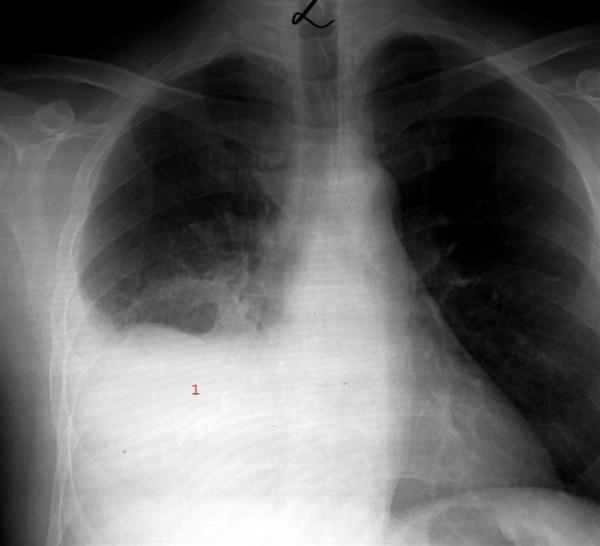

Lungebetennelse i nedre del av høyre lungeDersom en person får symptomer på luftveisinfeksjon som er mer alvorlig eller mer langvarig enn en vanlig forkjølelse, vil det være aktuelt å ta kontakt med helsetjenesten. I Norge vil det i de fleste tilfeller være mest hensiktsmessig å ta kontakt med fastlegekontoret og utenfor kontortidene med legevakt. Ved alvorlig pustebesvær eller andre alvorlige symptomer bør man ringe 113.

Typisk sykehistorie og funn ved legeundersøkelsen er noen ganger nok til at legen stiller diagnosen. Blodprøver som høy CRP, høy senkning eller økt antall hvite blodlegemer styrker mistanken om lungebetennelse. Imidlertid viser forskning at det alltid vil være knyttet noe usikkerhet til en diagnose stilt på denne måten. Sikkert bevis for at det foreligger lungebetennelse, får man fra et røntgenbilde eller eventuelt en annen egnet bildeundersøkelse av lungene.